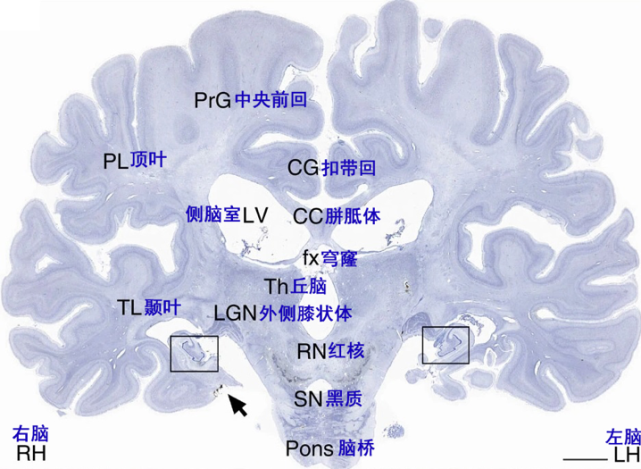

图片

图5 H.M.去世后大脑组织尼氏染色切片,方框及箭头所指为海马